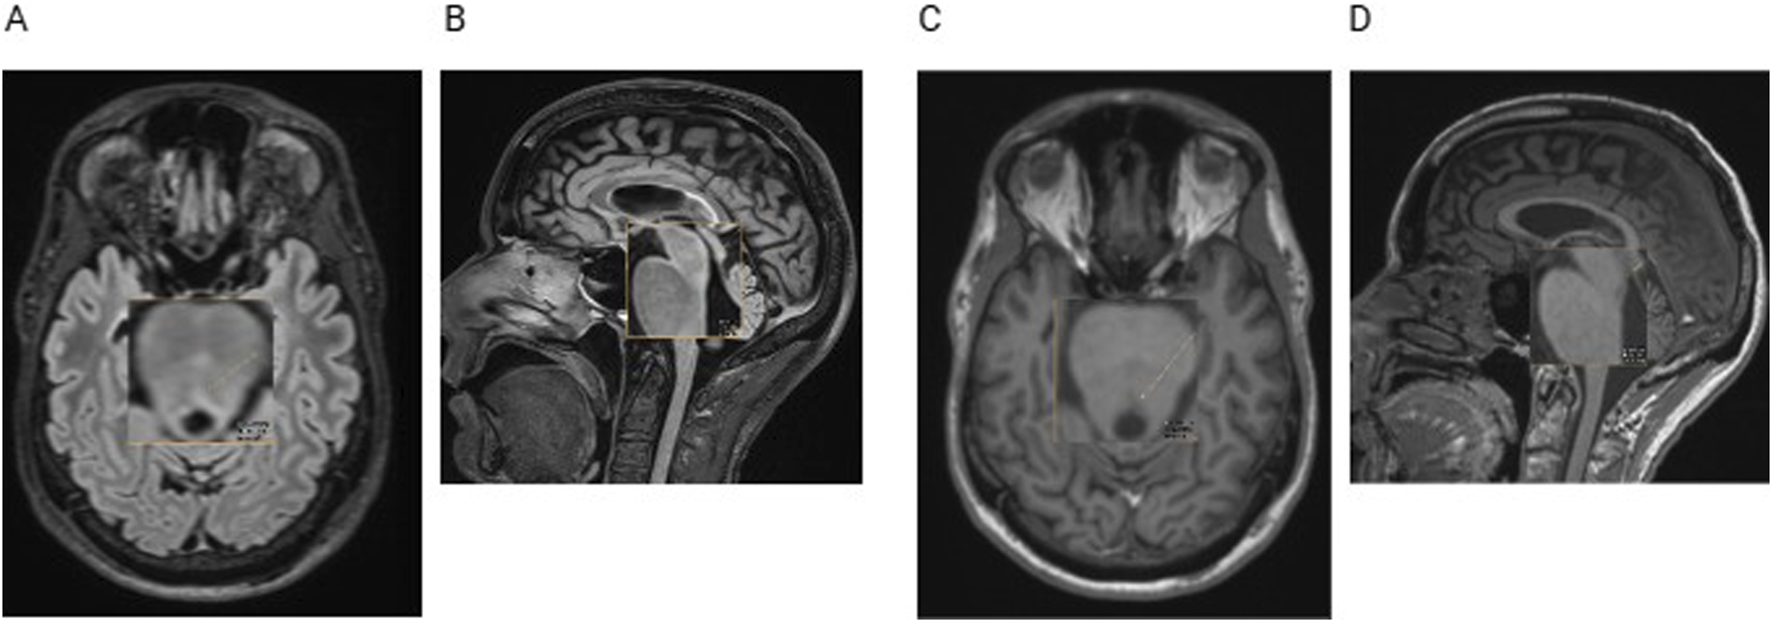

Upon reevaluation of the patient’s cerebral magnetic resonance imaging (MRI), we found a midbrain lesion of the MLF that had not previously been described (Figures 4A–D).

FIGURE 4

Cerebral MRI with transversal (A) and sagittal (B) fluid-attenuated inversion recovery (FLAIR) sequences and with transversal (C) and sagittal (D) T1-weighted sequences. The orange arrow indicates a small demyelinating lesion, not described in the radiological reports before.